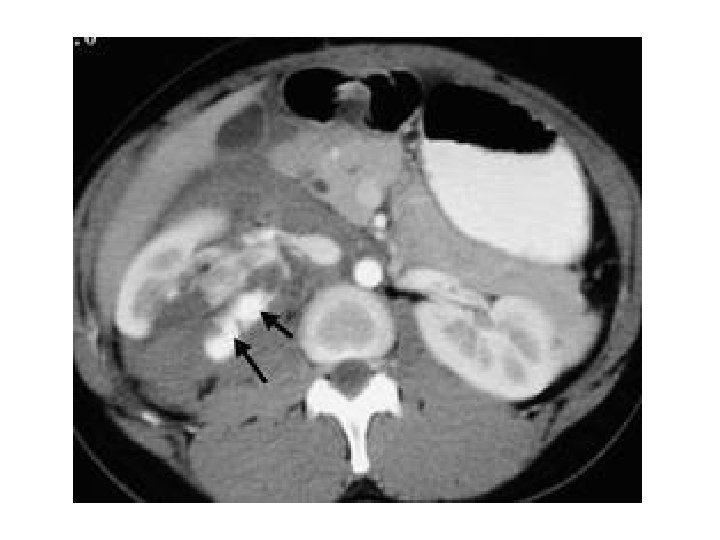

Case (5) • Elderly male patient with painless hematuria and weight loss.